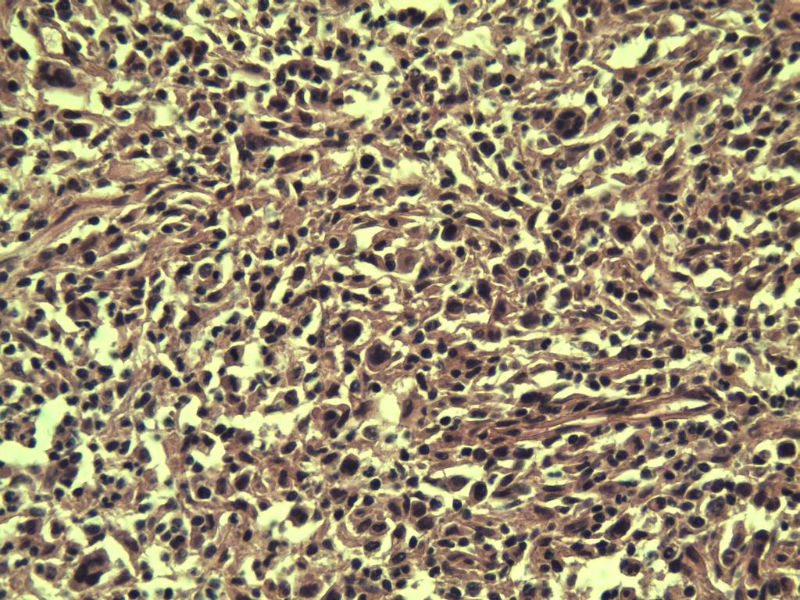

男,38岁,腹股沟 多枚淋巴结活检  直径 0.2-0.5 请各位老师看看 是什么 谢谢了!

"畏寒,发热咳嗽1年,加重伴腹部疼痛2月" 2月前患者感腹部疼痛不适伴大便呈稀大便,量不详,伴腰骶部疼痛,胸片:纵膈及右肺门多发性淋巴结肿大,进一步完善胸部CT:右肺及中叶病变,纵膈及肺门多发淋巴结肿大,结核性可能,脾脏增大,PPD(-),1个月来患者出现中上腹食欲不振,体重进行性消瘦,全身疲乏无力,3天前到医学院就诊,腹部B超:右肝囊肿,胆囊壁毛糙,脾大,胰周多个减弱回声,淋巴结不能除外,腹水,血常规示:WBC16.36x109 /L,N%14.25%,RBC2.63x1012/L ,HGB 66g/L 。右侧腋窝及腹股沟可扪及多枚淋巴结,压痛,无明显粘连。

腹股沟 多枚淋巴结活检图2

副皮质区增生,纤维化显著,细胞呈多形性,有一些多核巨细胞及一些异型细胞,病理性核分裂易见,胞浆红染,散在的小淋巴细胞,T细胞淋巴瘤不能除外,树突细胞肉瘤等鉴别。免疫标记。CD21、CD3、CD5、CD10、CD20、CD79a、PD1、CD68、CXCL13、KI-67、CD68、CD163等,据切片选择。不知对否。

淋巴结正常结构破坏,可见大的异型细胞,上皮样或梭形,恶性肿瘤,依据病史,首先考虑淋巴造血系统疾病,大中小细胞混杂,大细胞多,形态多样,可见多核瘤细胞,除以上考虑外需鉴别间变大、组织细胞肉瘤、指状突/树突细胞肿瘤、HL等,还需排除肉瘤或癌转移,尽管病人年轻,加上ALK、CK、S-100、CD1a。